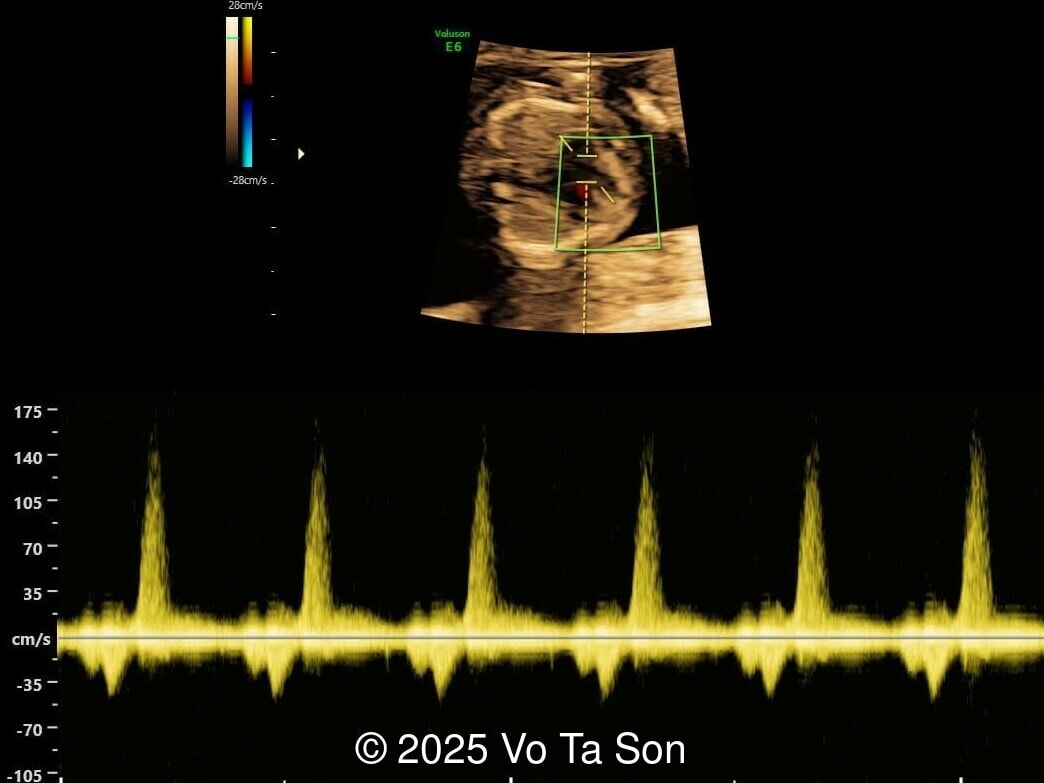

A woman underwent routine prenatal screening at 13 weeks. The non-invasive prenatal test (NIPT) showed low risk for common aneuploidies including trisomy 21, 18, and 13. However, first-trimester anomaly scan revealed multiple fetal anomalies.

Please describe the abnormalities and provide a syndromic diagnosis that best fits the presentation.